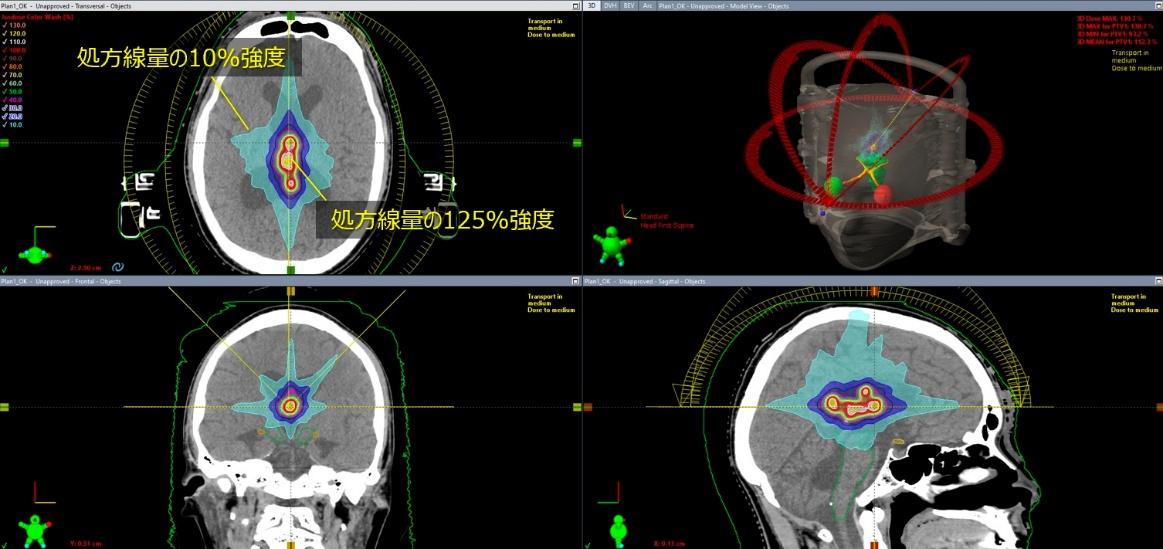

多発性脳転移SRS専用アプリケーション(Elements Multiple Brain Mets SRS)

Elements Multiple Brain Mets SRS は、複数の脳転移に対する定位放射線治療(SRS)の治療計画を効率的に作成するためのソフトウェアです。脳内に複数存在する転移性腫瘍に対して、それぞれの病変を正確に捉えながら放射線を集中させる治療計画を、自動化・最適化することができます。

本ソフトウェアでは、MRIやCT画像をもとに病変の位置や形状を解析し、複数の腫瘍に対して同時に高精度な照射計画を作成することが可能です。これにより、腫瘍には十分な線量を届けながら、周囲の正常脳組織への影響を可能な限り抑えた治療を目指します。

また、治療計画作成の効率化により、患者さんの治療準備にかかる時間の短縮にもつながります。このように、Elements Multiple Brain Mets SRS は、複数の脳転移に対して安全性と精度の高い定位放射線治療を実施するための治療計画支援システムです。